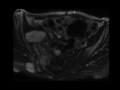

Unilateral Sacroiliitis from Tuberculosis

CT and MRI images demonstrate destruction of the right sacroiliac joint with edema along both ides of the joint and a contiguous fluid collection. This was discovered to represent tuberculosis of the joint in a patient with significant TB-related active lung disease (not shown).